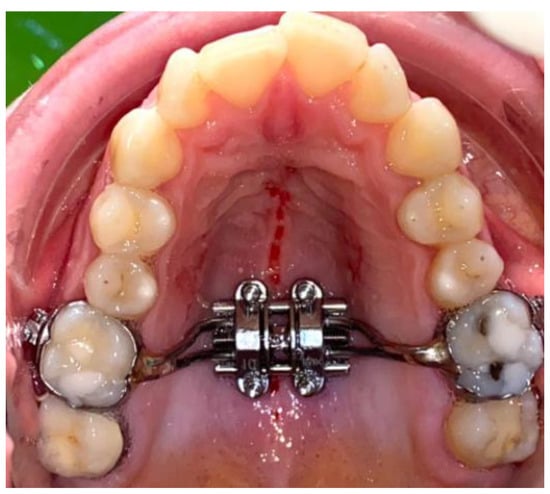

2. Material and Method

2.1. Outcome Measures

2.2. Clinical Outcomes